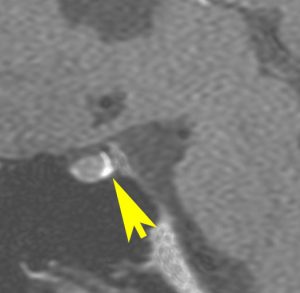

下にお見せするのは実例です。11歳で尿崩症で発症,初潮が発来せず,18歳で低身長を指摘され下垂体機能不全とMRIにてLCHを疑われました。HCGは測定限界値以下で経過しました。

左側のMRIは21歳時のものです。発症後10年が経過していました。

腫瘍性病変が増大したために,経蝶形骨洞手術 TSS で生検術を計画しました。経鼻手術でしたので,受け持ちの若い先生が,入院後に3Dやらthin sliceやら濃厚なCT検査を2度行いました。

予定どおり生検したのですが,大学病院病理部から帰ってきた返事は「免疫染色を含めて腫瘍細胞はなく,小型リンパ球を中心とした多彩な炎症細胞浸潤を認めることからlymphocytic hypophysitisの可能性は考えられます」という返事でした。

私は,生検術が終わってから初めて,手術前にCT検査が繰り返されたことを知りました。

「生検」術直後のMRIです。腫瘍がかなり縮小しています。手術ではトルコ鞍底部の腫瘍をごくわずかに摘出しただけなので,手術前の頭蓋CT,胸部写真などのX線被曝によって腫瘍細胞が消失してしまったと考えられます。